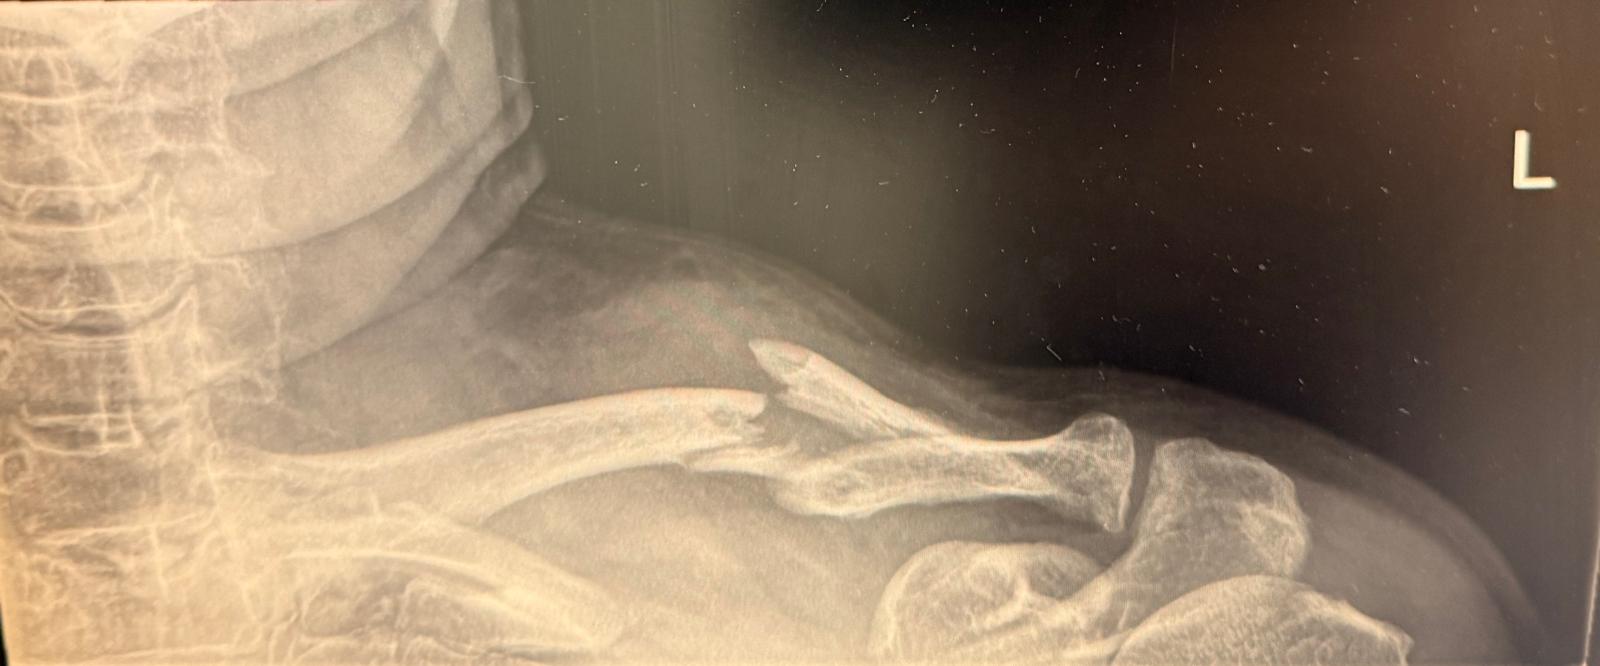

Obr. č. 2 – 27.12.2024

Na RTG snímke je jasne viditeľná zlomenina kľúčnej kosti, pri ktorej došlo k posunutiu jednotlivých častí kosti. Okrem toho je možné rozpoznať aj odlomený úlomok, ktorý naznačuje, že zranenie bolo pomerne vážne. Tento obrázok pomáha lekárom presne určiť rozsah poškodenia a rozhodnúť o ďalšom postupe liečby.